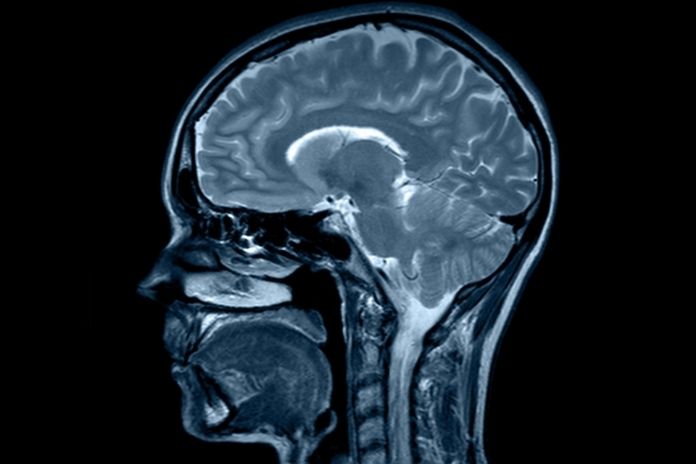

“Brain rot” describes the mental haze from digital overload, burnout, or endless scrolling, not a formal diagnosis. In medical terms, it aligns with grey matter reduction, neural inflammation, and weakened connectivity detected in MRI studies.

Recent 2026 imaging research, including voxel-based morphometry, links heavy internet use and media multitasking to prefrontal grey matter loss, mimicking early cognitive strain.

Modern habits trigger structural shifts. Chronic exposure to stress, screens, and poor recovery protocols can lead to measurable brain changes via MRI and fMRI.

How Scientists Measure “Brain Shrinkage”

Neuroimaging techniques, such as MRI with voxel-based morphometry, quantify grey matter density.

Key areas include:

- Hippocampus volume is tied to stress and memory.

- Prefrontal cortex thickness, for focus and self-control.

- The anterior cingulate cortex regulates emotions.

Even small gains in sleep or exercise boost density via neuroplasticity.

The table below summarizes common measurement targets and their linked functions, drawn from recent MRI protocols.

Longitudinal MRI studies confirm that consistent cardio, 30 minutes daily for several months, thickens grey matter in memory and mood centers. This enhances cognitive resilience and reverses stress-induced atrophy.

- Grey Matter Loss Is Measurable: MRI studies confirm shrinkage in key areas from chronic stress, digital overload, and inflammation, not just “feeling off,” but structural shifts.